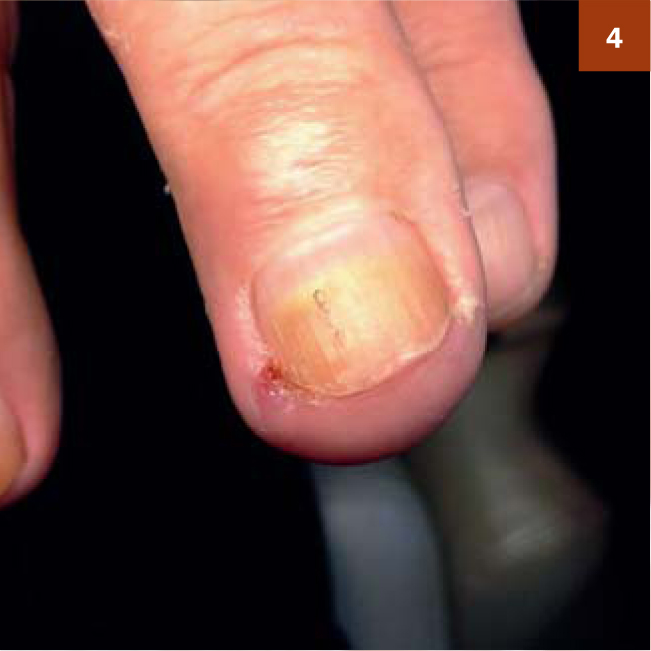

2-я стадія - врослий ніготь з набряком і запаленням (фото 3).

Ця стадія - провісник гнійного процесу, тому дуже важливо провести процедуру за всіма правилами гігієни і антисептики. Робимо трьох-п'ятихвилинну теплу ванночку з сіллю. Обробляємо палець антисептиком (хлоргексидин, перекис, октенисепт або їх аналоги обов'язково повинні бути в арсеналі майстра). Кут необхідно округляти або видалити, якщо є така можливість. Найчастіше повністю видалити врослий кут вдається на другий процедурі, через кілька днів. Потім повторно обробити антисептиком, зробити пов'язку. Будинки клієнт кожен день повинен робити ванночки і міняти пов'язку, також можна застосовувати спиртові настоянки. Через кілька днів, коли набряк спаде і обробку буде зручніше проводити в кабінеті, можна повторно скруглить кут. Контакт з водою необхідно виключити, так як це

джерело інфекції (фото 4).